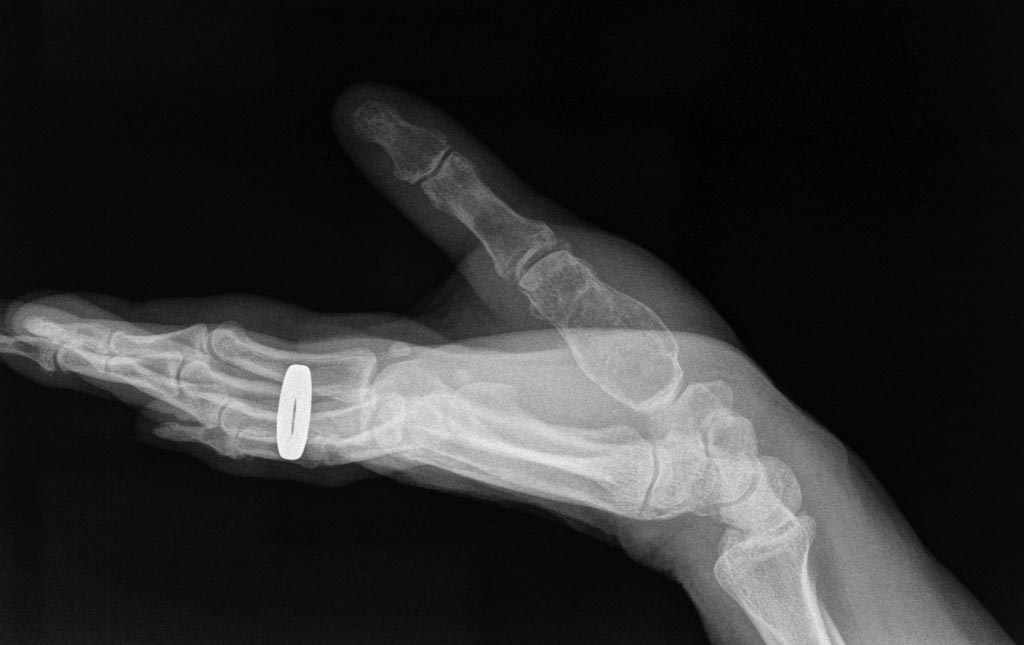

[Ortho] Опухоль 1 пястной кости.

Уважаемые коллеги помогите с диагнозом и дальнейшей тактикой

лечения.Боли беспокоят в течении года,в последнее время не может

писать,и резко снизилась сила хвата кисти.